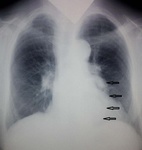

1.Саркоидоз....медиастинальная форма

2. Мета в бронхопульмональные....

Первая мысль о саркоидозе.Ну, а где здесь про стандарт?

Для 90 лет ТАКАЯ аорта не редкость...в прямой проекции явное ПРОДОЛЖЕНИЕ тени к клюву аорты...что с корнями - тоже 90 лет?